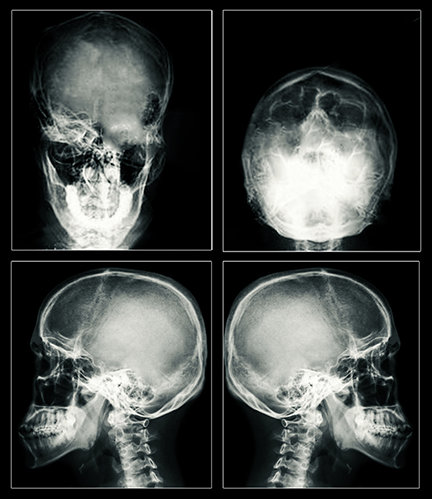

Az eredmény ugyanaz: epilepsziás nagyroham és agykárosodás, amely tartós is lehet. A nagymértékben megnövekedett elektromos áram lyukat üthet az agysejteken, ezáltal elpusztítva őket. Az elektromosság hőt is generál, amely szintén elpusztíthatja a sejteket. Az ECT-páciensek MRI-felvételein agyzsugorodás és hegek láthatók, amelyek az okozott kár vitathatatlan bizonyítékai.